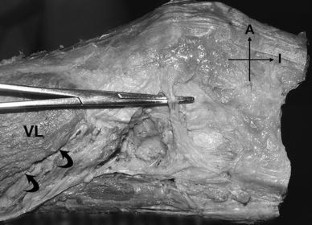

Most descriptions of the extensor mechanism of the knee do not take into account its complexity and variability. The quadriceps femoris insertion into the patella is said to be through a common tendon with a three-layered arrangement: rectus femoris (RF) most superficially, vastus medialis (VM) and lateralis (VL) in the intermediate layer, and vastus intermedius (VI) most deeply. We dissected 20 limbs from 17 cadavers to provide a more detailed description of the anterior components of the knee: the tendon, the patellar retinacula, and the patellofemoral ligaments. Only three of the 20 specimens exhibited the typically described quadriceps pattern. The remainder had bilaminar and even more complex trilaminar and tetralaminar fiber arrangements. We found an oblique head of the vastus lateralis (VLO), separated from the longitudinal head by a layer of fat or fascia, in 60% of the specimens. However, we found no distinct oblique head of the vastus medialis (VMO) in any specimen. The medial patellofemoral ligament (MPFL) was more common than the lateral (LPFL), supporting its suggested role as the principal passive medial stabilizer of the patella. Because the quadriceps muscle group plays a direct role in patellofemoral joint function, investigation into the clinical applications of its highly variable anatomy may be worthwhile with respect to joint dysfunction and failures of TKAs.

Fig. 3